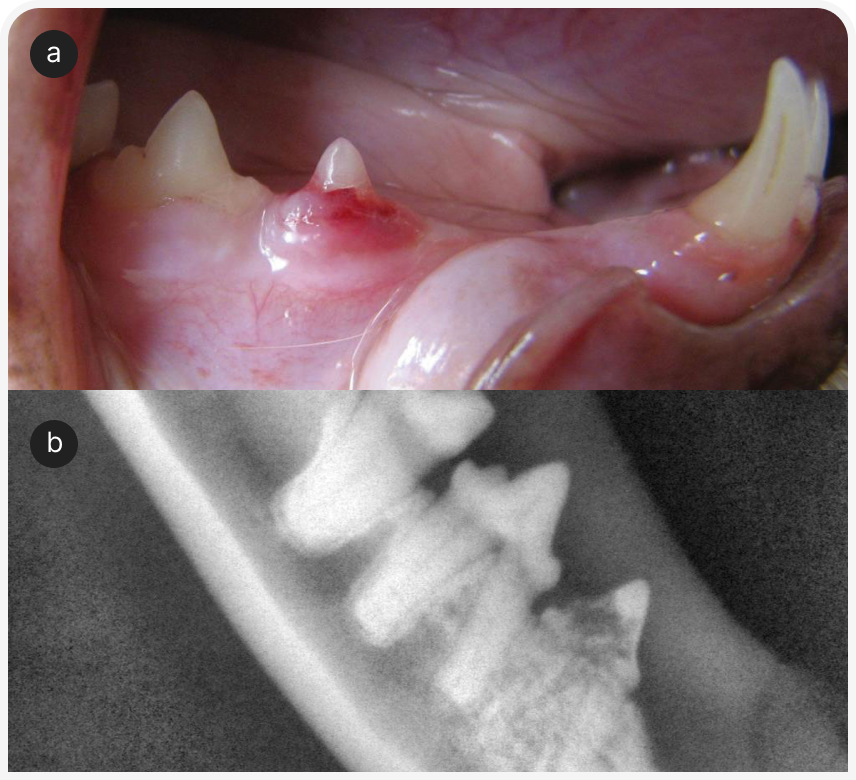

Часто в таких случаях бывает полезно повторить непосредственное обследование, поскольку исходно можно упустить из виду или не принять во внимание незначительные отклонения. Если ранее не определяли балльную оценку мышечной массы, следует сделать это и записать результат. Осмотреть ротовую полость у бодрствующей кошки часто непросто, но значимую патологию можно выявить уже при осмотре зубов и края десен. Однако важно иметь в виду, что беглый визуальный осмотр не позволяет исключить выраженного и клинически значимого заболевания зубов; тяжесть болезненных состояний, таких как резорбция корня зуба, можно определить только рентгенографически (Рисунок 1) (1). Следует провести тщательное офтальмологическое обследование для выявления симптомов увеита или хориоретинита. Эти симптомы неспецифичны, но часто наблюдаются у кошек при грибковых или протозойных инфекциях (Рисунок 2) (2). Нужно тщательно обследовать любые кожные или подкожные узелки, особенно в области внутренних парастернальных лимфоузлов. Также разумно понаблюдать за движениями кошки, чтобы выявить признаки заболеваний суставов, позвоночника или нервной системы; обычно кошек осматривают на столе и поэтому не замечают изменений походки, координации или силы мышц.

При стоматологическом обследовании было подтверждено заболевание пародонта легкой степени и проведено его лечение. При гистопатологическом исследовании биоптатов желудка и двенадцатиперстной кишки была выявлена лимфоплазмоцитарная инфильтрация легкой степени; при биопсии подвздошной кишки и толстой кишки — гистиоцитарная инфильтрация с разрастанием дрожжей в пределах поражения (по внешнему виду, Histoplasma capsulatum).